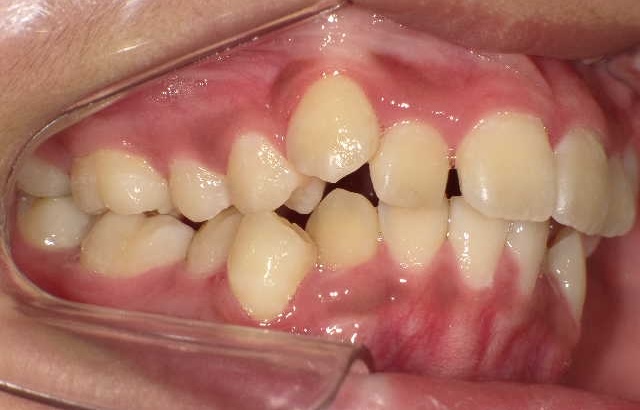

症例1-①

症例1-①の写真をご覧ください。著しく顎が小さく左の上下犬歯の萌出スペースがほとんどありません。ここで、歯ならびの相談に行くとおそらく将来、永久歯を抜くことになると言われることでしょう

口腔内を見ただけで、検査をすることなく、ショックな宣言を受けますが、そこには、医学的根拠による何の説明はありません。ここで、多くの場合、この二つのパターンのことを言われるでしょう。永久歯が生えそろってからきてください、またはとりあえず、顎を広げる治療してみましょう。